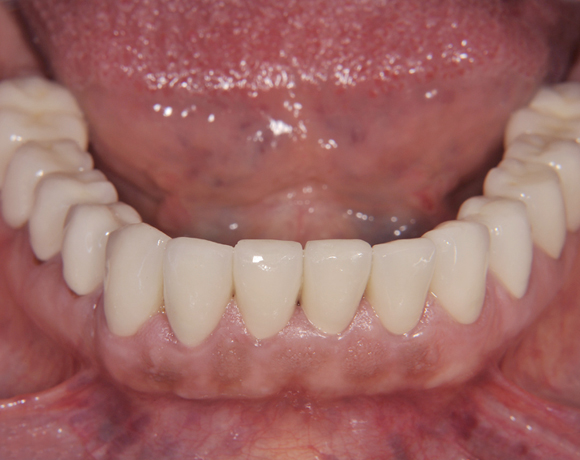

Der vorliegende Patientenfall zeigt eine komplette Neuversorgung der vorhandenen Metallkeramikkronen mit vollkeramischen Restaurationen. Zusätzlich wurde im Oberkiefer die Zahnreihe mit zwei Implantaten, für die fehlenden Molaren, ergänzt. Da keine ausreichende Knochenhöhe vorhanden war wurde ein interner Sinuslift geplant.